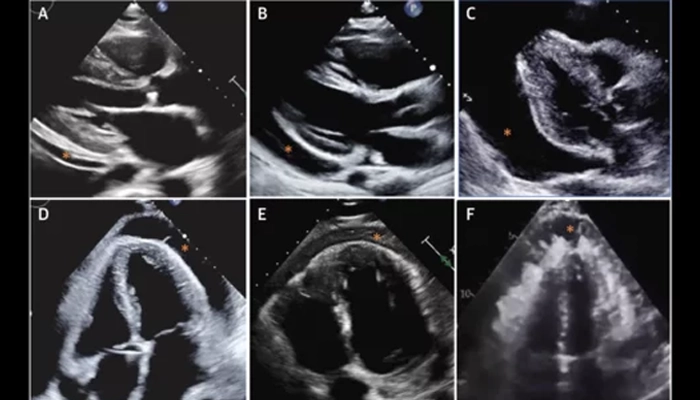

Siêu âm tim (Echocardiography): đánh giá lượng dịch màng ngoài tim(Pericardial Effusion - PEff), chức năng tim, có chèn ép hay không.

Đánh giá kích thước tràn dịch màng ngoài tim bằng siêu âm tim. Đại diện (A) PEff nhỏ, (B) PEff vừa, và (C) PEff lớn (∗). Đại diện (D) PEff đơn giản với các sợi fibrin, (E) PEff xuất tiết, và (F) PEff ác tính (∗) do u trung biểu mô màng ngoài tim